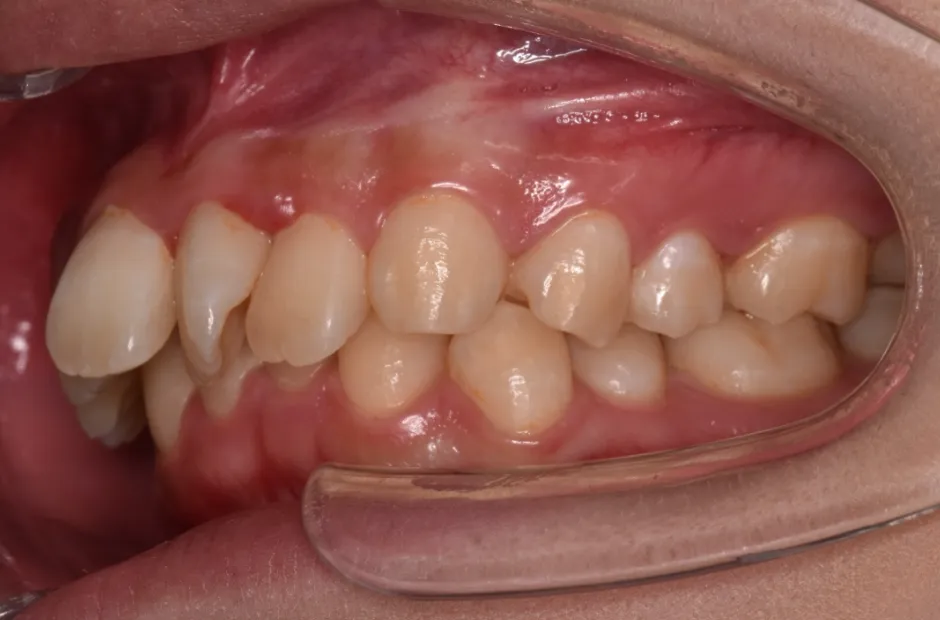

すきっ歯

| 診断名・主訴 | すきっ歯 |

|---|---|

| 年齢・性別 | 22歳・女性 |

| 治療期間・回数 | 2年半 30回 |

| 治療に用いた主な装置 | アンカー |

| 抜歯部位 | なし |

| 治療費 | 100万円(税抜) |

| リスク・副作用 | 装置による違和感・疼痛・歯肉退縮・歯根吸収・虫歯のリスクなど |

治療前

治療中

治療後